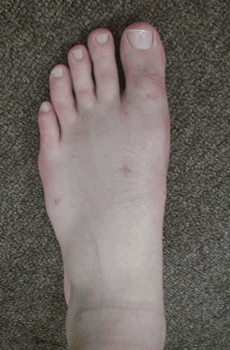

Caso 1: Hallux Valgus del adolescente